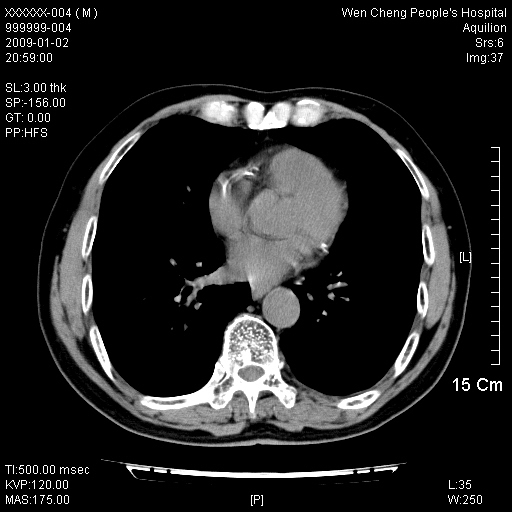

男性,73岁,有慢支病史,肿瘤系列标志物检验正常,血沉及血常规正常

右肺下叶背段小片状 磨玻璃样模糊影,内见血管及含气支气管像,支气管管壁增厚。考虑:慢性炎症!

1)不排除右肺下叶周围型肺癌可能;建议追踪复查。2)左右冠状动脉钙化。

右肺下叶背段小片状 实性与磨玻璃样影,内见血管及含气支气管像,支气管管壁增厚,边缘见长毛刺影。考虑:慢性炎症或肿瘤!建议抗炎治疗复查,密切观察随访!

右肺下叶片团状影内见扩张的含气支气管和支气管管壁增厚,其周有磨玻璃样模糊影和长毛刺。考虑慢性炎症可能性大。

2、右肺下叶片团状影内见扩张的含气支气管和支气管管壁增厚,其周有磨玻璃样模糊影和长毛刺。考虑周围型肺ca可能,结核不排。

高度提示细支气管肺泡癌,建议抗炎治疗半月观察病灶变化,如无明显改变,建议立即手术治疗.

病变形态非常不好呀,临床上血常规及症状也不明显,不太支持炎性病灶,高度警惕肿瘤病变,最好做个纤支镜检查。